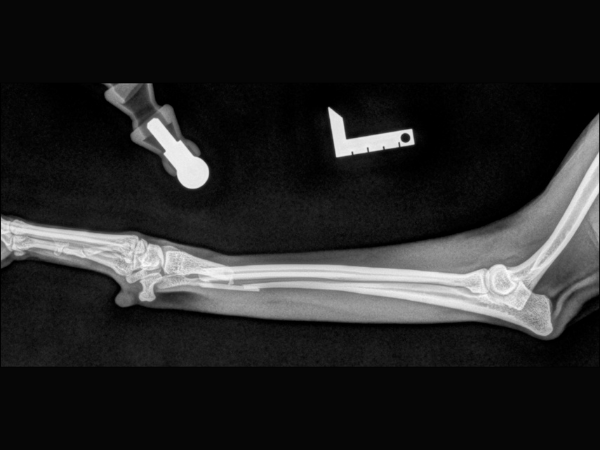

<術前のレントゲン>

左橈尺骨遠位端が骨折しています。